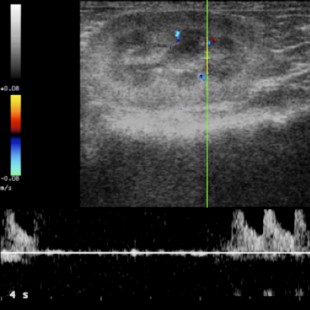

Ecografia

É muito útil para avaliar os tecidos moles dos nossos pacientes. Não é um meio invasivo e não emite radiação como a radiografia. É fundamental para muitos diagnósticos e tratamentos de urgência.